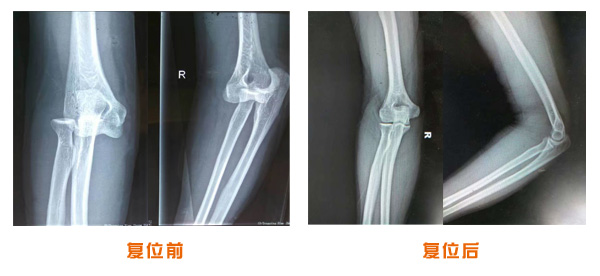

肥城市安駕莊梁氏骨科醫院是一所以梁氏手法正骨配合膏藥為特色的現代化??漆t院。

梁氏骨科術始創于清雍正年間,歷經八代,至今已有三百年歷史。據1929年泰安縣志載“梁瑞圖先生,字增生,號蓮峰,安駕莊人,精岐黃并發(fā)明接骨,凡跌打車凡跌打車軋皮不破而碎骨者......【詳細】 |